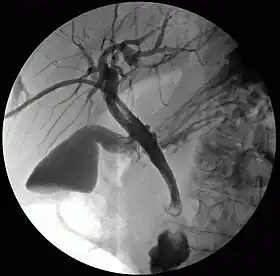

Percutaneous transhepatic cholangiography

Cholangiography is the imaging of the bile duct (also known as the biliary tree) by x-rays and an injection of contrast medium.[1]

1. Percutaneous transhepatic cholangiography (PTC): Examination of liver and bile ducts by x-rays. This is accomplished by the insertion of a thin needle into the liver carrying a contrast medium to help to see blockage in liver and bile ducts.